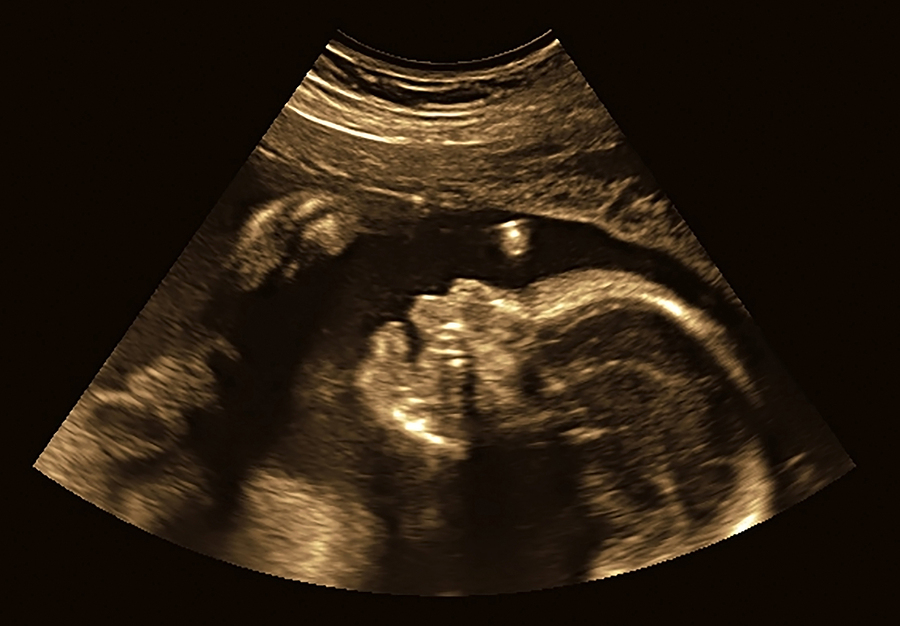

Pregnancy and giving birth was rather easy for me. But that isn’t the case for everyone. And what happens when you come home with your new bundle of joy is the biggest adjustment of all. Many people don’t know what to expect, especially with their first...

I haven’t mentioned much about what things were like those four days while I was in the hospital; but mistake my lack of words up until this point as a sign that things weren’t. It was rather the opposite. Because I’m an expat and I am still not...